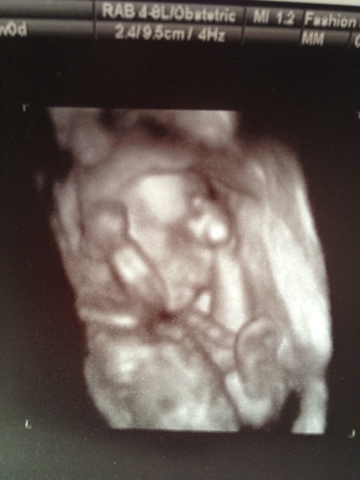

39 weeks

any symptoms: still a little achy, no contractions, but Monday I was 3cm dilated, my cervix is still 80% effaced, you're head is at a -2 station still

baby name: Ellison, still deciding on your middle name, may happen just before we leave the hospital